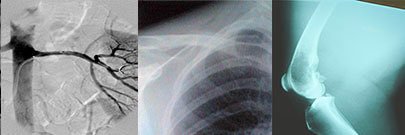

Providing patient-first care, training tomorrow's radiology leaders, and discovering solutions at the intersection of health care, science, and technology